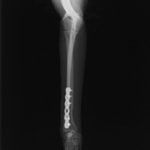

他院にて左大腿骨遠位の成長板骨折(salter-harrisⅠ型)が認められており、治療相談を目的として来院。当院にて、キルシュナーワイヤーを用いたピンニングにより骨折部位の整復を行いました。術後の経過は良好で、現在も経過観察中です。

術後レントゲン

機器

Arthrex社のターゲティングデバイスを用いてピンニングの位置を調整することで、確実な固定を行っています。当院ではこの手術器具以外にも、人の手術にも使用される様々な器具を導入し、手術精度を高め、また医療メーカーと新しい器具の開発、試作にも取り組んでおります。